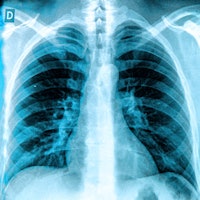

2. CT lung cancer screening packs sessions

To be sure, interest in CT lung cancer screening at RSNA has been building for at least a decade. But at this year's meeting, coming less than two weeks after the monumental decision by the U.S. Centers for Medicare and Medicaid Services (CMS) to reimburse for the scans in high-risk smokers, there wasn't an empty seat in room 404CD.

Several more studies over the years supported the notion that CT-screened patients were living longer. But lacking a control group, other factors such as lead time bias and length bias could have potentially accounted for their longer survival. Finally, with publication in 2011 of results from the National Lung Screening Trial (NLST), which showed a minimum 20% mortality reduction, there was no longer any doubt that screening was a lifesaver. The question was whether private payors and the government would foot the bill.